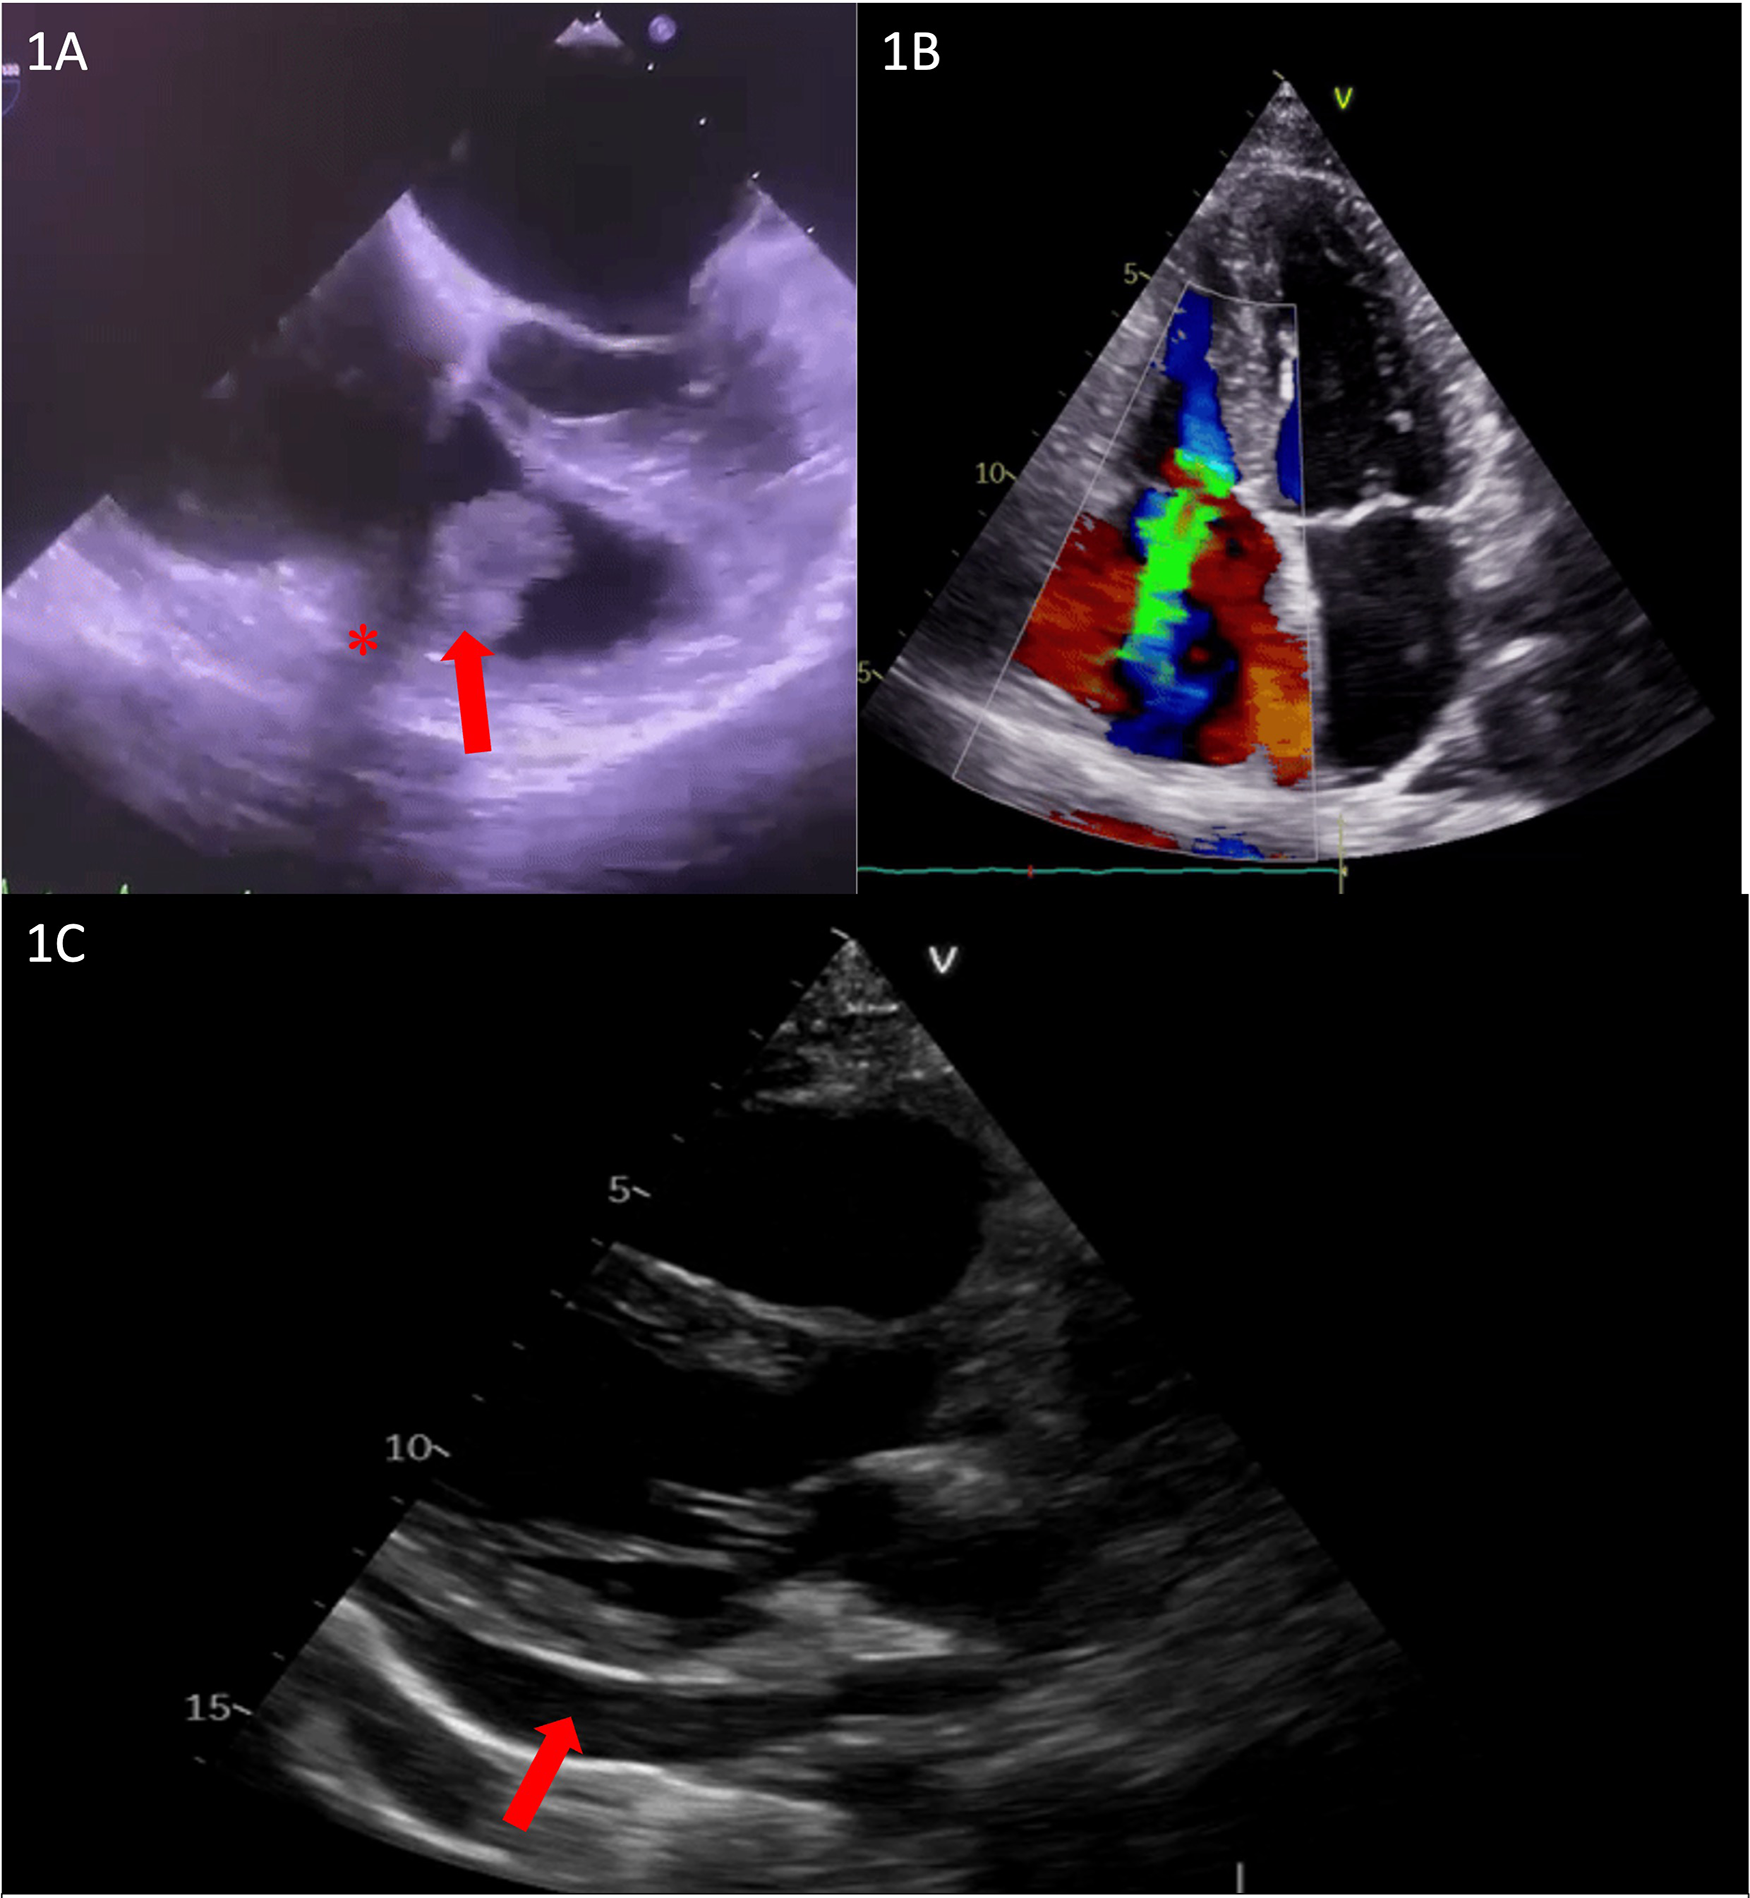

We present the case of a 39-year-old woman, 24 weeks pregnant with a history of drug abuse, who was initially admitted to the Cardiology Department with symptoms of fatigue, fever, and shivers. She was hemodynamically stable, with a blood pressure (BP) of 100/73 mmHg, slightly tachycardic at 105 bpm, and without hypoxemia. The patient had leukocytosis, systemic inflammatory response syndrome, anemia, and elevated NTproBNP values suggestive of heart failure. Transthoracic echocardiography (TTE) was performed, revealing a hyperechoic mass measuring 28 mm × 12 mm that was attached to the tricuspid valve on the ventricular side of the subvalvular apparatus and to the atrial surface of the cusp, with very high mobility and severe tricuspid insufficiency. The patient’s cardiac chambers were not dilated and there was no sign of other valvular involvement (Figures 1A,B).

Figure 1

(A) Transesophageal echocardiography showing subvalvular vegetation (red arrow) and unusual echocardiographic shadowing (red asterisk). (B) TTE showing severe tricuspid regurgitation. (C) Transthoracic echocardiography showing pericardial effusion up to 14 mm (red arrow).

A thorough clinical and imagistic assessment included blood cultures, an electrocardiogram, serial transthoracic echocardiography, transesophageal echocardiography (TEE) (Figure 1A), and pregnancy ultrasound, and a final diagnosis of tricuspid valve endocarditis was established, with blood cultures positive for Staphylococcus aureus. Although unusual echocardiographic shadowing was seen in TEE, it was considered an artifact (Figure 1A).

A multidisciplinary task force, consisting of a cardiologist, gynecologist, infectious disease specialist, psychiatrist, and cardiac surgeon, was assembled, deciding on a conservative treatment with antibiotherapy for 6 weeks while closely monitoring the pregnancy. After 4 weeks, the patient developed extreme thoracic pain and pericardial effusion (Figure 1C), leading to the urgent need for a computed thoracic scan to exclude right ventricular (RV) wall rupture or aortic dissection. The scan was conducted with correct fetal protection using two shields according to the current recommendations. Since no obvious mechanical complications were diagnosed at that time, it was considered infectious pericarditis and managed conservatively.